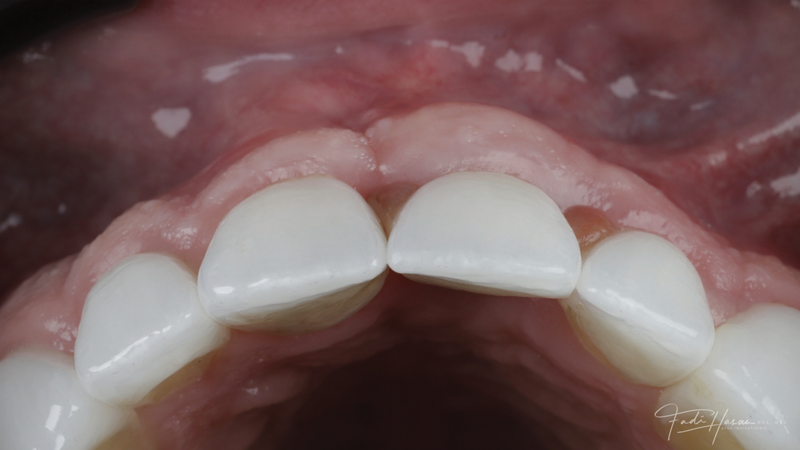

(11.) Preoperative close-up view of the tooth No. 9 site following implant placement and a period of healing, exhibiting a residual soft-tissue deficiency and an undulating facial soft-tissue morphology.

Figure 11